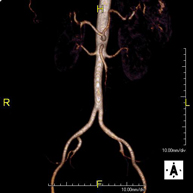

- Angio RM Aorta-ilíaca

Prueba diagnóstica no invasiva que consiste en el estudio de la arteria aorta abdominal de las arterias ilíacas, obteniendo imágenes de alta definición anatómica mediante el empleo de un campo electromagnético y ondas de radio (con un emisor y un receptor). Es indispensable el uso de contraste paramagnético (Gadolinio). Sin embargo, no utiliza radiación ionizante. La calidad de las imágenes permite realizar reconstrucciones en 2D y 3D. Esta prueba está especialmente indicada como estudio pre-quirúrgico (mapa vascular) antes de intervenciones percutáneas o quirúrgicas de aorta abdominal y arterias ilíacas, estudio complementario en pacientes con isquemia de miembros inferiores, etc.

- Angio RM Arterial extremidades inferiores

Prueba diagnóstica no invasiva que consiste en el estudio vascular del sector aorto-ilíaco y de los vasos arteriales de ambas extremidades inferiores, obteniendo imágenes de alta definición anatómica mediante el empleo de un campo electromagnético y ondas de radio (con un emisor y un receptor). Es indispensable el uso de contraste paramagnético (Gadolinio). Sin embargo, no utiliza radiación ionizante. La calidad de las imágenes permite realizar reconstrucciones en 2D y 3D. Está especialmente indicado en aquellos pacientes en los que hay sospecha de enfermedad vascular de ambas extremidades, en pacientes con enfermedad vascular de ambas extremidades como el mapa vascular antes del tratamiento (percutáneo o quirúrgico), como el mapa vascular pre-quirúrgico en pacientes con lesiones óseas o musculares que requieran cirugía, etc.

- Angio-RM Aorta iliaca

Prueba diagnóstica no invasiva que consiste en el estudio de la arteria aorta abdominal, obteniendo imágenes de alta definición anatómica mediante el empleo de un campo electromagnético y ondas de radio (con un emisor y un receptor). Es indispensable el uso de contraste intravenoso paramagnético (gadolinio). Sin embargo, no utiliza radiación ionizante. La calidad de las imágenes permite realizar reconstrucciones en 2D y 3D. Esta prueba está especialmente indicada como estudio pre-quirúrgico (mapa vascular) antes de intervenciones percutáneas o quirúrgicas de aorta abdominal, estudio complementario en pacientes con isquemia de miembros inferiores…

- Angio-RM Arterial extremidades inferiores

Prueba diagnóstica no invasiva que consiste en el estudio de la arteria aorta abdominal, obteniendo imágenes de alta definición anatómica mediante el empleo de un campo electromagnético y ondas de radio (con un emisor y un receptor). Es indispensable el uso de contraste intravenoso paramagnético (gadolinio). Sin embargo, no utiliza radiación ionizante. La calidad de las imágenes permite realizar reconstrucciones en 2D y 3D. Está especialmente indicado en aquellos pacientes en los que hay sospecha de enfermedad vascular de ambas extremidades, en pacientes con enfermedad vascular de ambas extremidades como mapa vascular antes del tratamiento (percutáneo o quirúrgico), como mapa vascular pre-quirúrgico en pacientes con lesiones óseas o musculares que requieran cirugía…